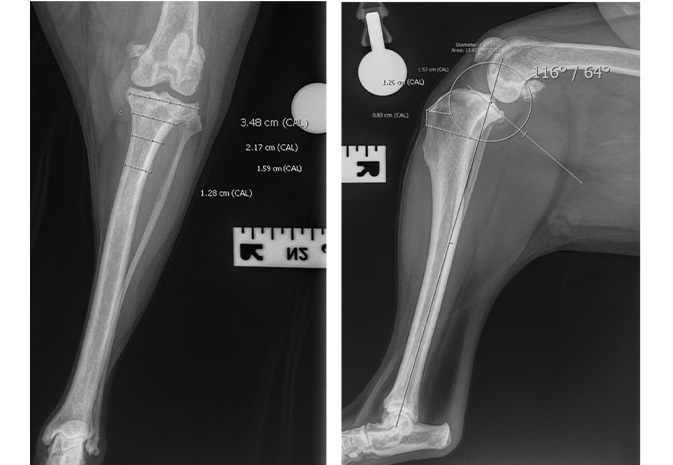

Before surgery, accurate measurements are taken from radiographs to determine the surgical action